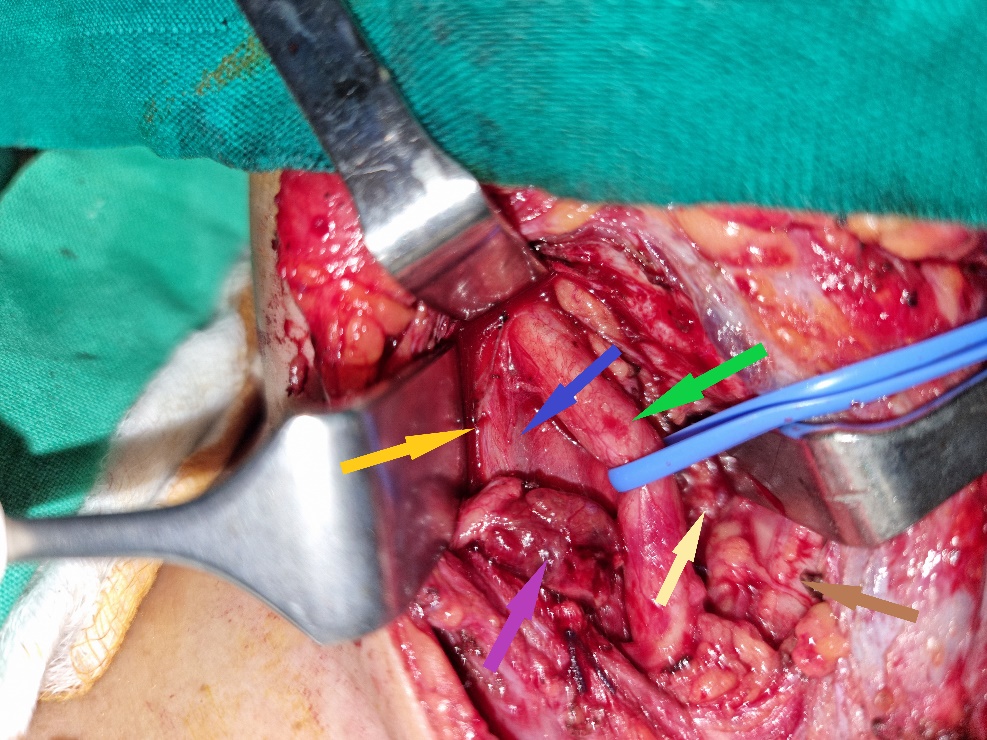

Green arrow — Right common carotid artery. Blue arrow — Right internal jugular vein. Purple arrow — Parathyroid adenoma. Yellow arrow — Right vagus nerve. Brown arrow — Trachea. Light brown arrow — Right recurrent laryngeal nerve (Courtesy Dr. V. Penopoulos)